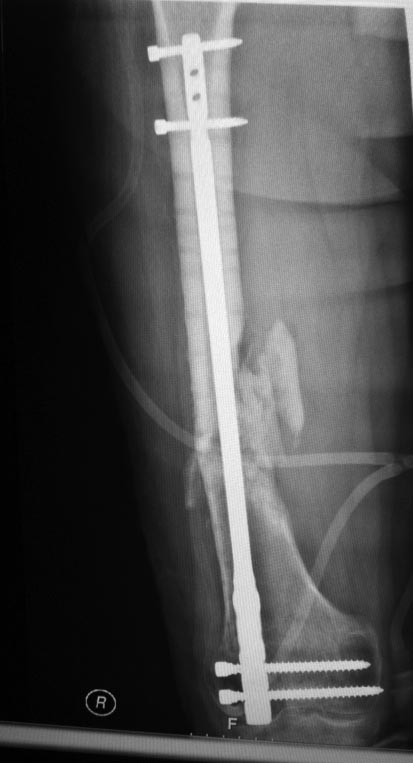

Re: ЛОЖНЫЙ СУСТАВ ПОСЛЕ БИОС

еще снимки